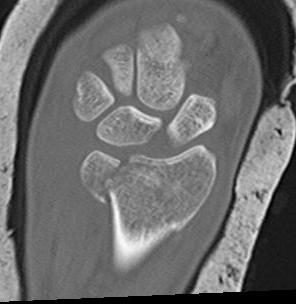

Distal Radius Fracture Articular Step Coronal CTDistal Radius Fracture Articular Step Sagittal CT

Articular incongruency > 2 mm

Distal Radius Fracture DRUJ incongruentDRUJ FractureDRUJ Fracture CT

Sigmoid notch disruption and DRUJ instability